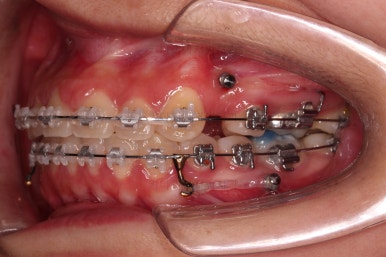

결손 부위에 미니스크류를 이용해서 뒤쪽 어금니들을 결손 부위로 앞으로 앞으로 계속 당겨줍니다.

얼굴모습에서의 중앙선도 지속저으로 체크하면서 한 쪽으로 치우침 없이 마무리를 해야 하고요.

틈새가 줄어들 때 까지 같은 작업을 반복합니다.

점점 틈새가 붙어가는게 보이죠?

계속 반복합니다.

틈새는 거의 다 붙어가는데 교합이나 중앙선 등을 위해 추가적으로 밀고 당기기를 해줍니다.

디테일을 좀 더 맞추고 부산치아교정 마무리를 합니다.

치아 갯수 및 사이즈 문제로 위아래의 정중선은 100% 일치시키긴 힘들지만 가능한 선에서 최대한 맞추었고요.

윗니가 1개 없는 상태에서의 교합도 잘 맞추고 마무리를 했습니다.

다시 틈새가 벌어지지 말라고 유지철사를 붙여주었고요.

물론 약간 다시 벌어질 수는 있으나 그 정도는 처음에 비하면 아무 문제도 아닌 정도죠.